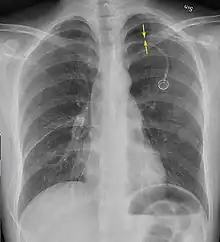

Anteroposterior inspired X-ray, showing subtle left-sided pneumothorax caused by port insertion -